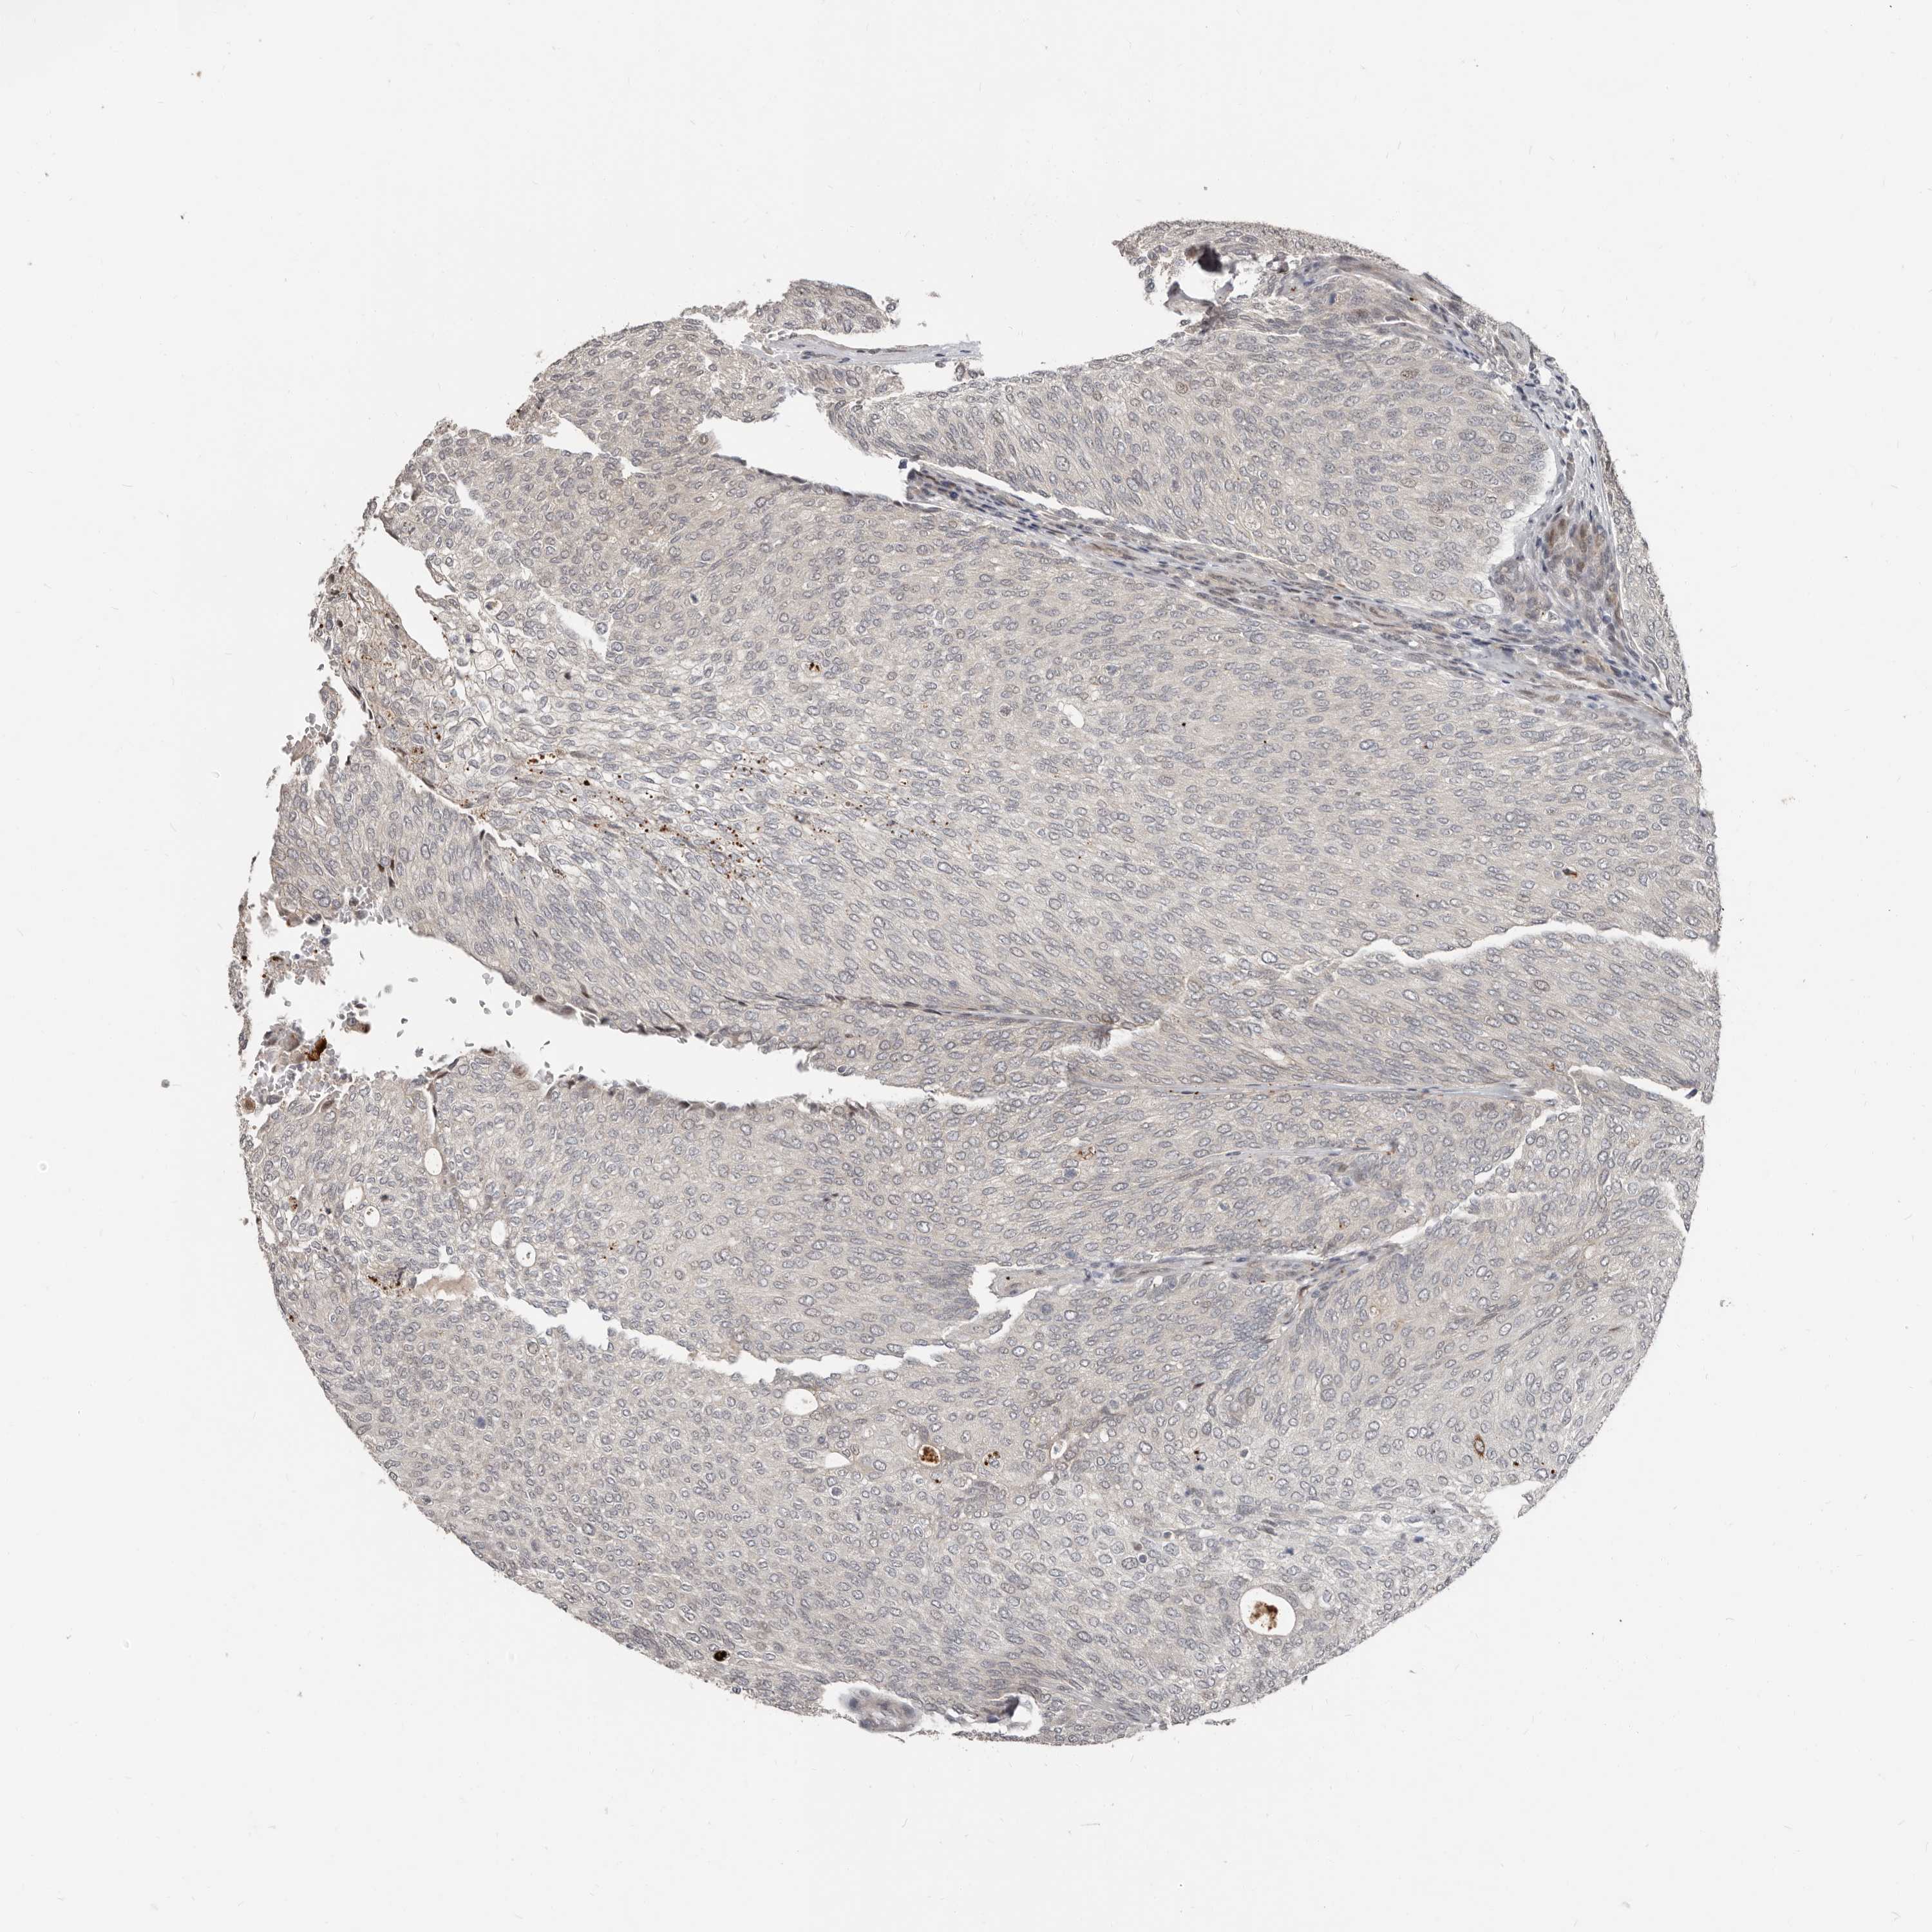

UROTHELIAL CANCER - Protein expressioni

A mouse-over function shows sample information and annotation data. Click on an image to view it in a full screen mode. Samples can be filtered based on level of antibody staining by selecting one or several of the following categories: high, medium, low and not detected. The assay and annotation is described here.

Note that samples used for immunohistochemistry by the Human Protein Atlas do not correspond to samples in the TCGA dataset.

Antibody stainingi

Antibody staining in the annotated cell types in the current human tissue is reported as not detected, low, medium, or high, based on conventional immunohistochemistry profiling in selected tissues. This score is based on the combination of the staining intensity and fraction of stained cells.

Each image is clickable and will lead to virtual microscopy that enables deeper exploration of all samples and also displays staining intensity scores, fraction scores and subcellular localization as well as patient and tissue information for each sample.

Antibody HPA029165

Antibody HPA029167

Antibody CAB028574

Staining

High

Medium

Low

Not detected

Intensity

Strong

Moderate

Weak

Negative

Quantity

>75%

75%-25%

<25%

None

Location

Nuclear

Cytoplasmic/membranous

Cytoplasmic/membranous,nuclear

Urothelial carcinoma, Low grade

Urothelial carcinoma, High grade